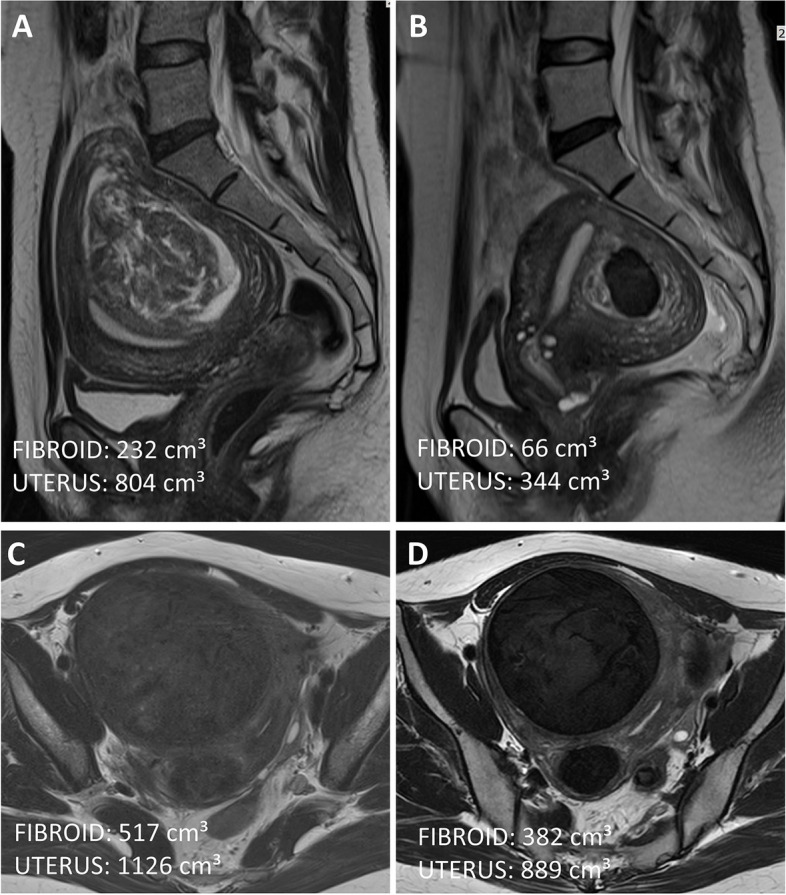

Methods: This is a retrospective cohort study of patients who underwent UAE for symptomatic uterine fibroid between December 2016 and January 2023 at our hospital. Changes in mean fibroid volume were compared based on MR images. Menstrual pain, excessive flow symptoms, and treatment satisfaction before UAE and 6 months after UAE were compared.

Results: A total of 149 premenopausal patients (mean age 45.7 ± 2.7 years) were included for analysis (FIGO 2/3, n = 57; FIGO 4-7, n = 92). Baseline menstrual pain, fibroid, and uterine volume before UAE were comparable between the two FIGO groups (p > 0.05). The menstrual flow index was higher for the FIGO 2/3 group (mean ± SD [min-max]: 9.4 ± 1.4 [4-10] vs 8.0 ± 2.3 [0-10], p < 0.001). Six months after UAE, the improvements in menstrual flow index (mean ± SD]: -3.7 ± 2.6 vs -2.6 ± 2.2, p = 0.035), fibroid volume (mean ± SD: -54.7 ± 21.7% vs -39.8 ± 16.2%, p < 0.001), and uterine volume (mean ± SD: -38.2 ± 16.3% vs -31.1 ± 11.6%, p = 0.008) in the FIGO 2/3 group were significantly higher than the FIGO 4-7 group. Both groups had comparable improvements in menstrual pain index (-2.1 ± 2.6 vs -1.8 ± 2.5, p = 0.008) and 88% of the patients were satisfied or very satisfied overall.